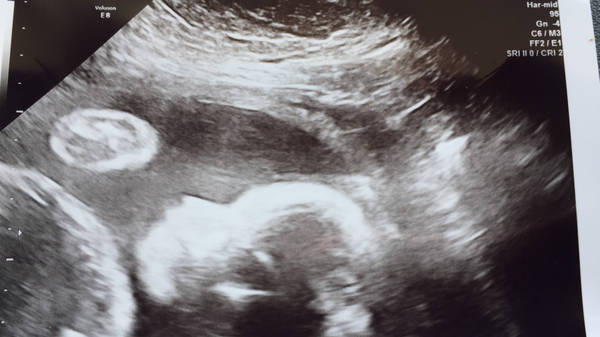

All good with scan. Bubs growing well. Now 2.4lbs :)

Blondes - what a gorgeous scan! I find now, at 14 months, I can still see the same side on profile of my DD as the scan picture at 20weeks. And yes, NZ care is a little bit blah. But that could just be my experience. My step mum in Auckland had a much better time with HG as up there she has specialists galore and could easily pay for private treatment and thus be treated magnificently.

Blondes A great scan picture. Lol about 'message withdrawn'. I hope no Ginger Pusher hypnotised you into a trance state, recommending 'ginger' Grin.

Lol no. Reliesed I had all name details and dob on scan so reported myself

blondes I'm so glad you got to see baby on a scan after your scare - and get such a lovely picture! Must be so reassuring for you Smile.